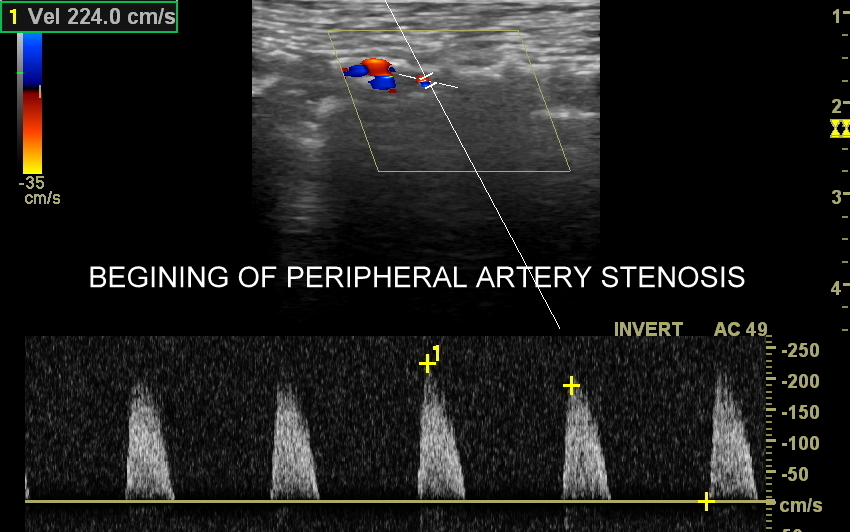

Choroby tętnic. Najczęstszą chorobą tętnic jest miażdżyca, która naturalnie i powoli rozwija się wraz z wiekiem, jednakże może ulec znacznemu przyspieszeniu i nasileniu pod wpływem takich czynników jak palenie papierosów, cukrzyca, zaburzenia lipidowe, czy nadciśnienie tętnicze. Rozwijająca się miażdżyca doprowadza do zwężeń naczyń tętniczych, a czasem nawet do ich zamknięcia wywołując objawy niedokrwienne. Przykładami ostrych chorób niedokrwiennych jest udar mózgowy oraz zawał serca. Z kolei przykładami przewlekłych zespołów związanych z miażdżycą są demencja, angina brzuszna i chromanie przestankowe. Inne choroby tętnic obejmują m. in. tętniaki, rozwarstwienia, zapalenia, czy zespoły podkradania, których cech poszukuje się w trakcie wykonywania badania USG Doppler tętnic.

Badanie USG Doppler tętnic, klasyczne badanie angiograficzne oraz badanie angio-TK to podstawowe i uzupełniające się metody diagnostyczne naczyń. Badanie dopplerowskie w przeciwieństwie do dwóch pozostałych jest metodą oceny funkcjonalnej a nie tylko wizualnej, tzn. oprócz stopnia zwężenia tętnicy ocenia również zaburzenia przepływu w oraz za zwężeniem, a także zaburzenia ukrwienia dystalnego tkanek.

Badanie USG Doppler tętnic kończyn dolnych wykonywane jest najczęściej w ramach diagnostyki miażdżycy zarostowej tętnic kończyn i jej objawów w postaci chromania przestankowego, czyli bolesności łydek, rzadziej ud i pośladków, pojawiających się w trakcie wysiłku fizycznego. Inne wskazania do USG tętnic kończyn dolnych obejmują uczucie chłodnych stóp, marznięcie nóg, diagnostykę zespołu zespół  Raynauda, czy choroby Buergera. W stanach nagłych badanie wykonuje się w przypadku ostrego niedokrwienia np. na tle obwodowej zatorowości tętniczej. Rzadsze patologie, które pojawiają się w obrębie tętnic kończyn dolnych to tętniaki prawdziwe, tętniaki rzekome (pseudotętniaki) i rozwarstwienia. Tętniaki rzekome są zwykle efektem powikłań jatrogennych nakłuć, a rozwarstwienia wynikiem urazów tętnicy, np. podczas uprawiania sportu.

Podczas wykonywania USG Doppler kończyn dolnych bada się osie tętnicze obu kończyn, które obejmują takie tętnice jak tętnica udowa wspólna, powierzchowna, głęboka, podkolanowa, tętnica piszczelowa przednia, tylna i tętnica strzałkowa. Ocenia się również ewentualne zwężenia oraz tzw. krążenie oboczne; poszukuje się cech zatorowości, zapalenia, rozwarstwienia i cech tętniaków.